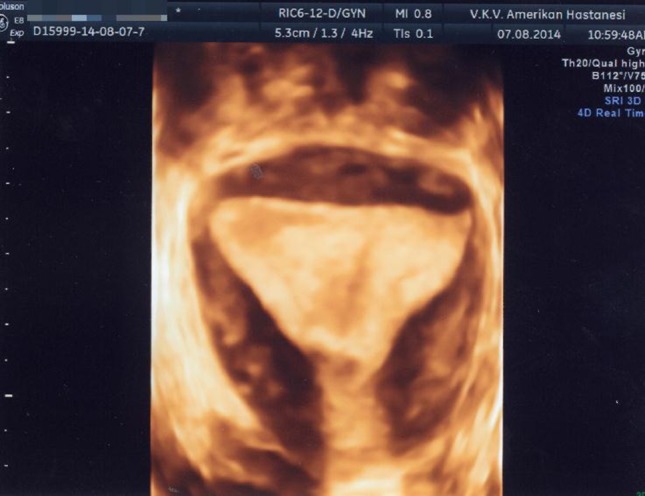

تصویر سه بعدی از رحم کمانی شکل. لطفا توجه داشته باشید که در حالی که کانتور خارجی رحم طبیعی است، فرورفتگی خفیف فوندال در حفره وجود دارد.